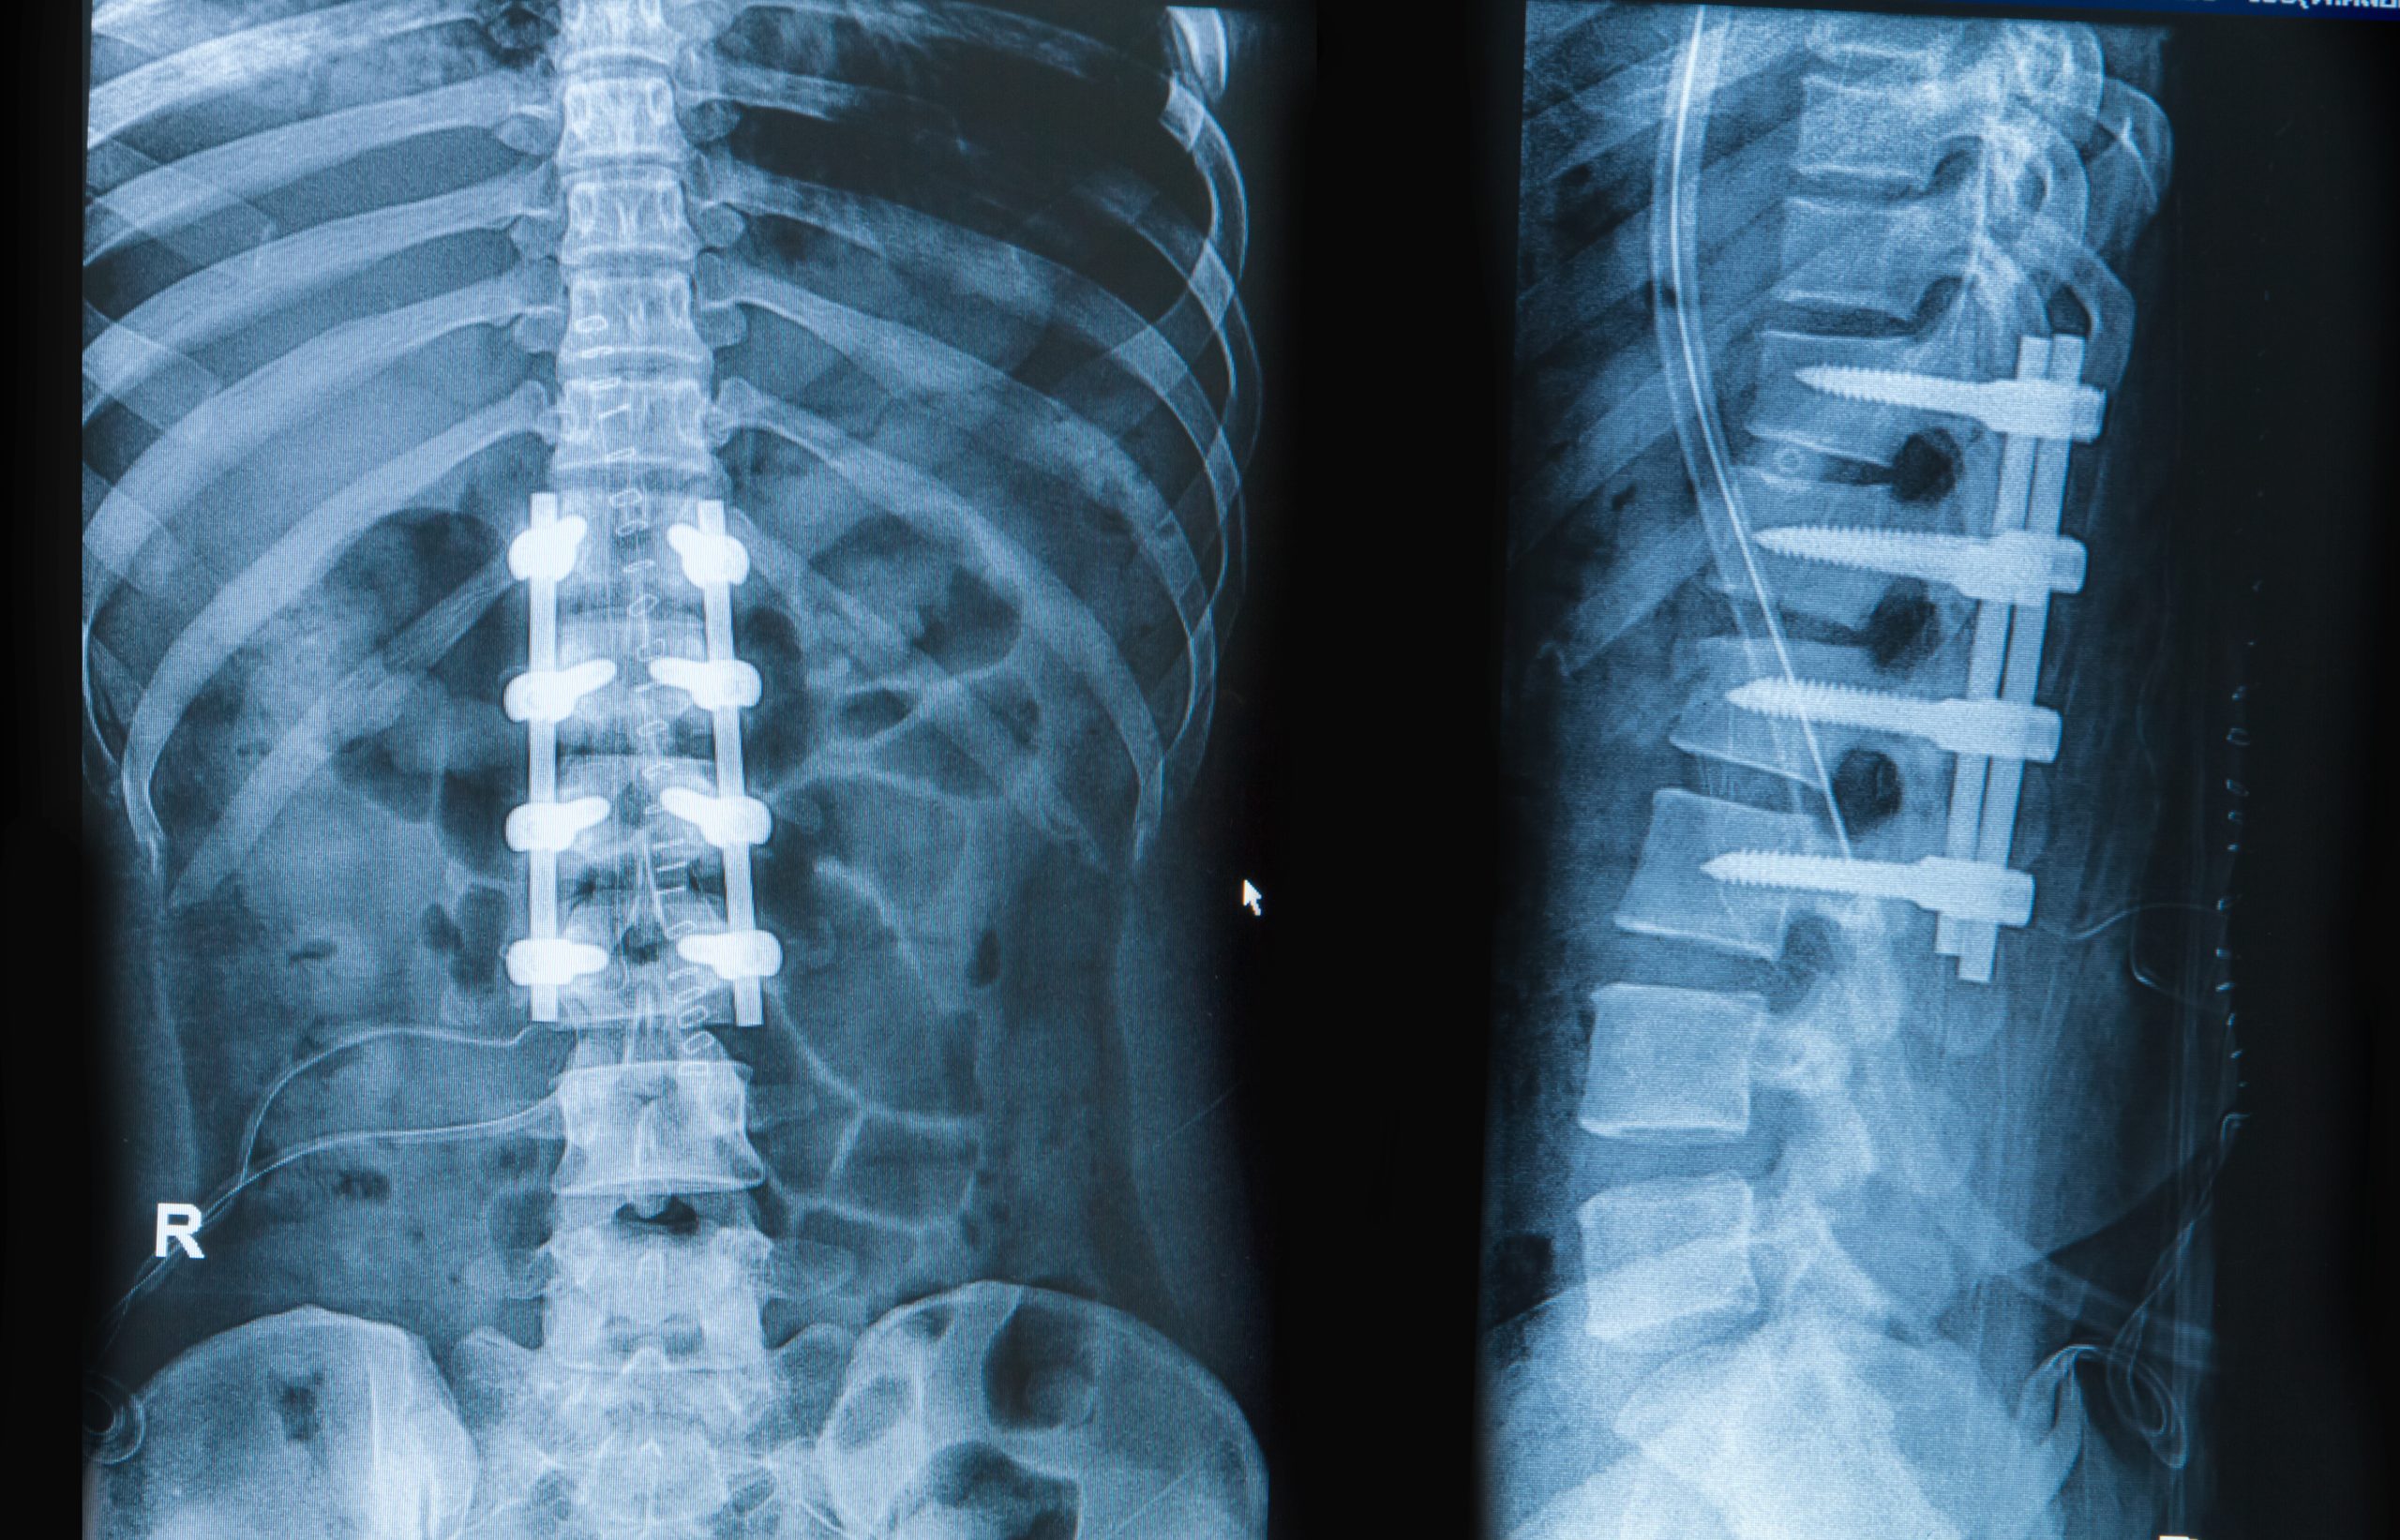

Spinal implants represent advanced medical devices designed to restore stability, correct deformities, and alleviate pain in patients suffering from various spine conditions. These sophisticated hardware systems include rods, screws, plates, cages, and artificial discs engineered to support the spine during healing while maintaining proper alignment and function throughout the recovery process.

Fusion Hardware Systems

Spinal fusion implants, like those used in 360 fusion, include pedicle screws, rods, and interbody cages designed to permanently join two or more vertebrae together, eliminating motion at problematic spinal segments. These systems provide immediate stability while bone grafts grow and fuse the treated levels, creating a solid bridge between vertebrae over several months.

The primary benefits of fusion hardware include excellent pain relief for conditions like degenerative disc disease, spondylolisthesis, and spinal deformities. One common example is Transforaminal Lumbar Interbody Fusion (TLIF), which accesses the disc space from the side to relieve nerve compression and restore disc height. These systems offer proven long-term durability and success rates.